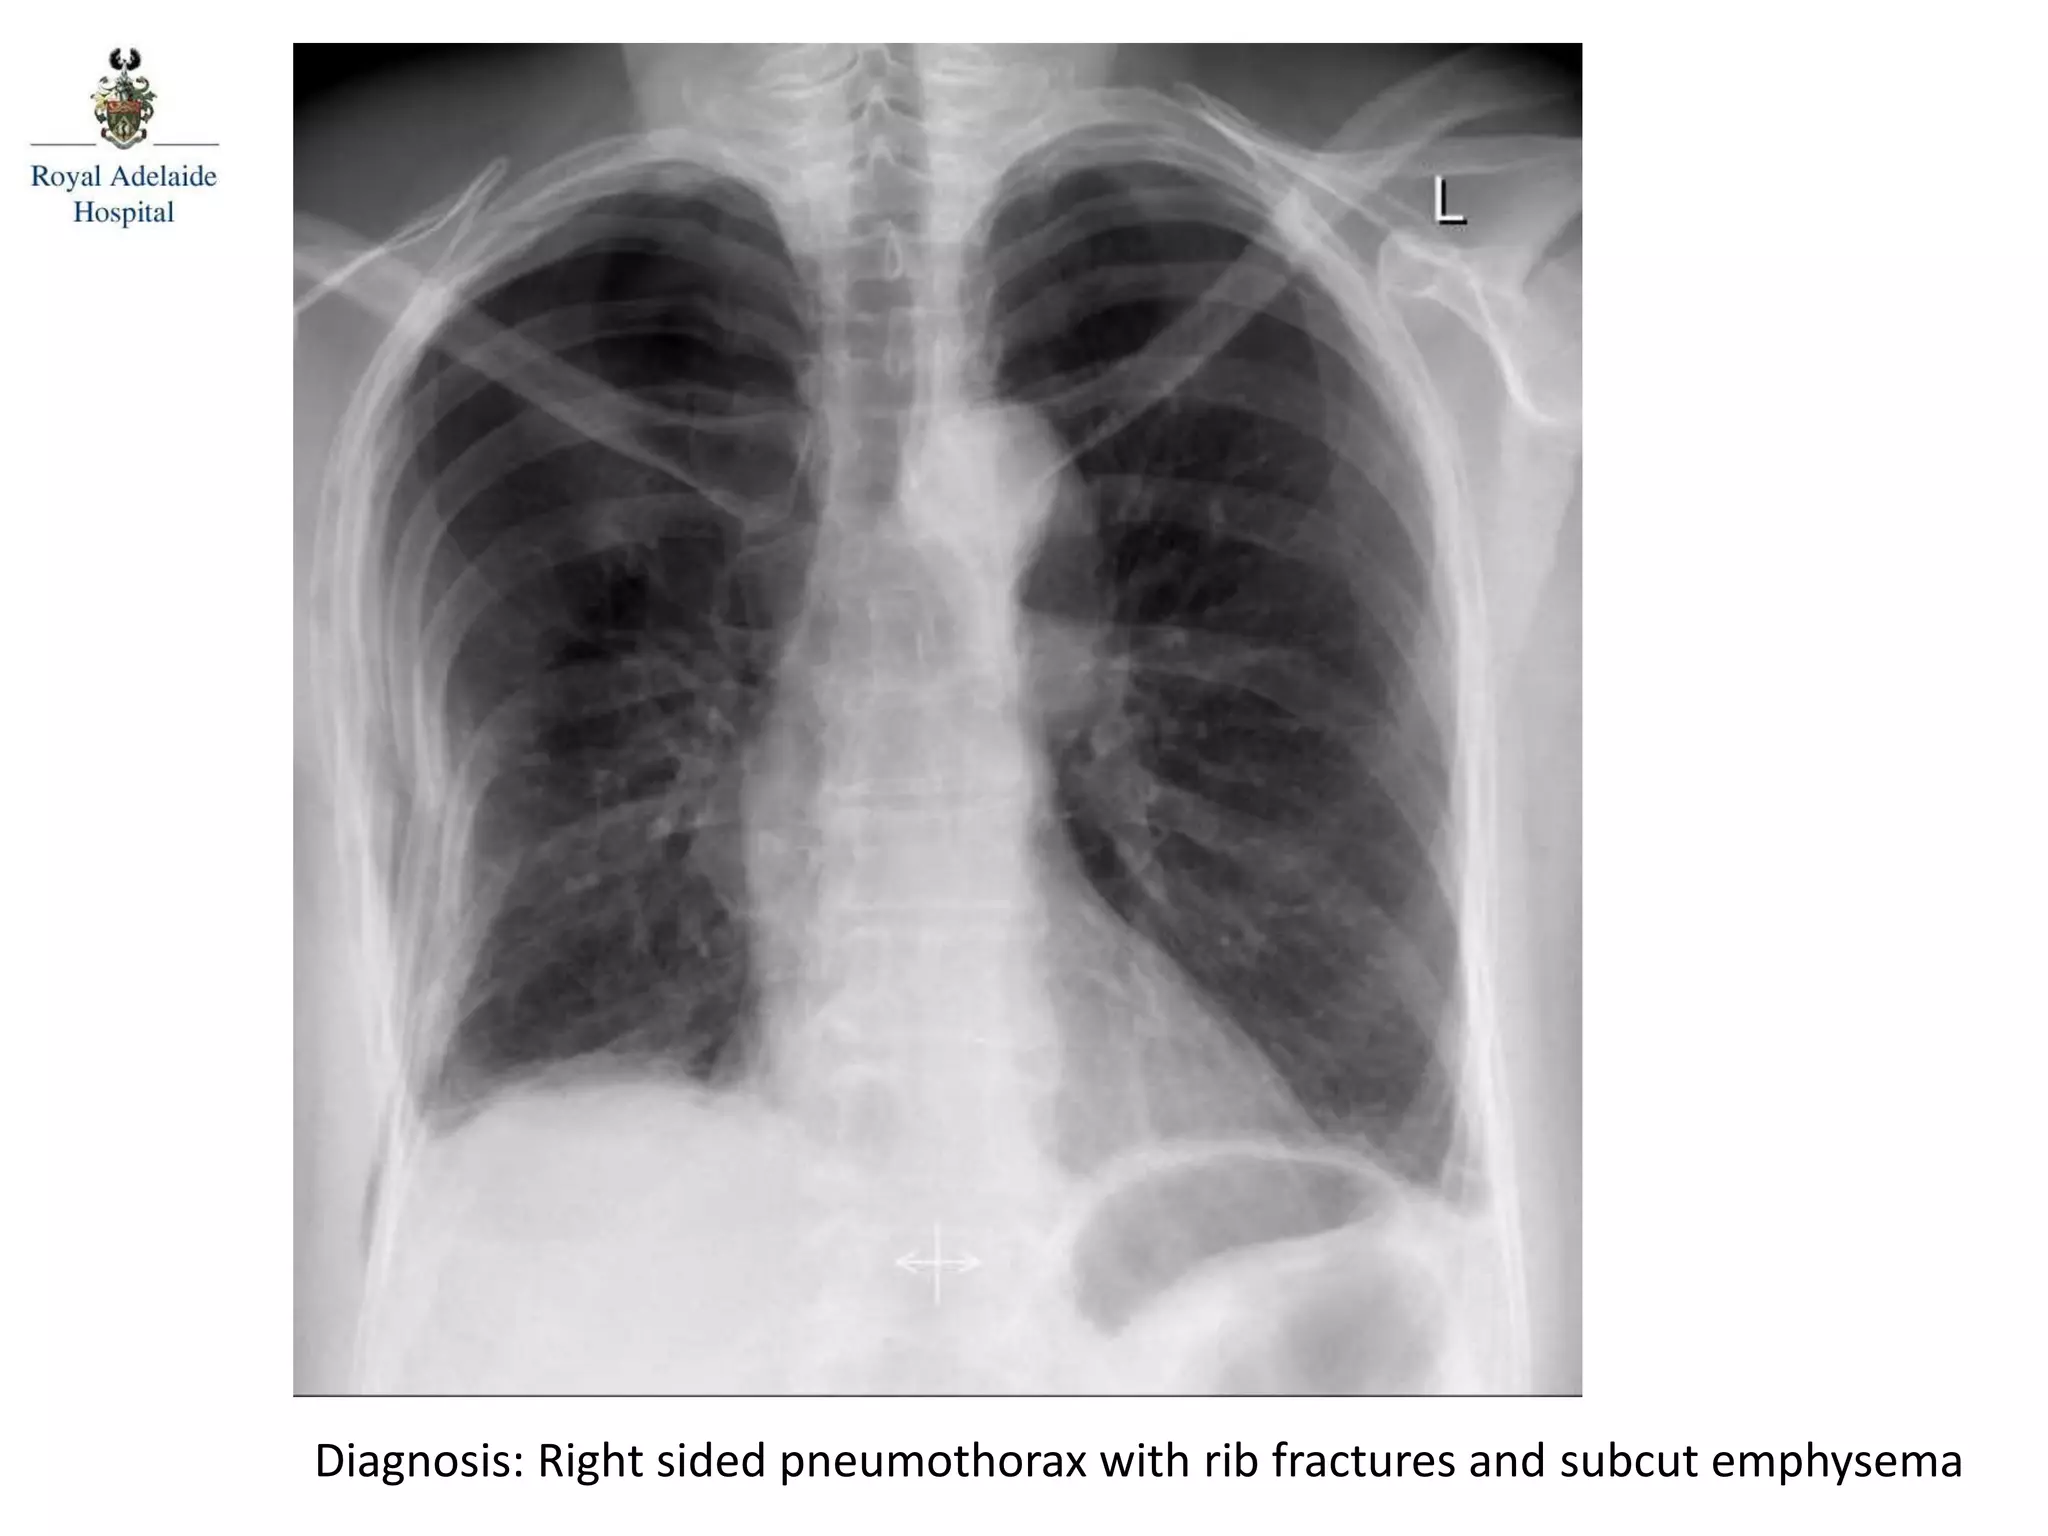

Diagnosis: Right sided pneumothorax with rib fractures and subcut emphysema